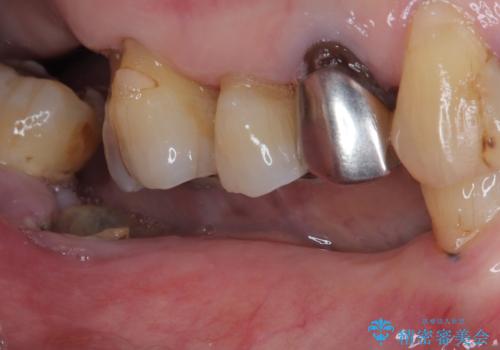

- 奥歯がなく、作ってもらった入れ歯もうまく使えないため、インプラント治療を希望して来院された患者様です。

入れ歯を装着すると咬み合わせの位置が大きく変化することが、入れ歯を使用できない理由でしたが、とにかく煩わしいのでインプラント治療を行いたいとのことでした。

インプラント埋入時に仮歯を装着させることが可能な安定値が得られたため、その日に仮歯の装着を行いました。

咬合時に仮歯が噛み合わないように調整はしたのですが、反対側の奥歯も欠損していることから、食事中積極的に仮歯で咀嚼をしてしまい、2週間後には大きく安定値が低下してしまいました。